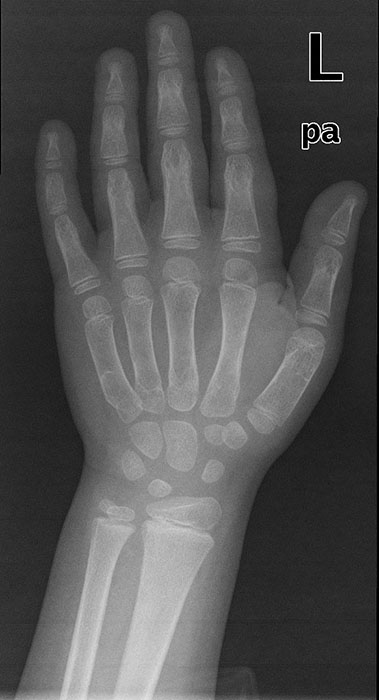

<p>This patient is 6 years old. What pathology do they have?</p>

This patient is 6 years old. What pathology do they have?

Delayed bone age